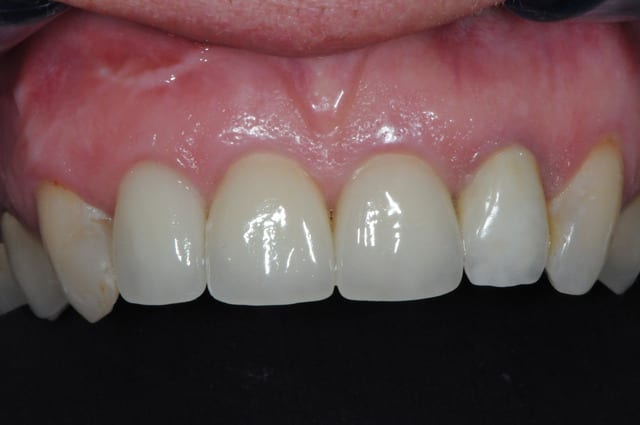

voici - voilà:

photo

1: j+ 2 ou 3 jours

2: j+8 mois

3-4-5: j+ 2 ans

sur la photo 3 on voit à la gencive que l'aspect est moins granité au niveau du col.

c'était ça l'indice pour trouver Charlie.